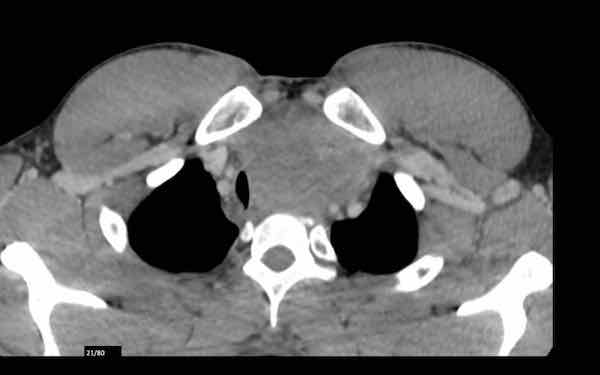

Ca lâm sàng 2

Các hình ảnh này của một bệnh nhân nam 43 tuổi có đau ngực.

Hình ảnh

Có một khối ở trung thất trước mạch máu.

Bờ không đều và tổn thương dương tính trên PET-CT.

Thảo luận

Chẩn đoán có khả năng nhất là thymoma, có thể là thể xâm lấn hoặc thậm chí là ung thư tuyến ức.

Tiếp tục xem phim chụp tiền phẫu hai tháng sau…

Hai tháng sau, một phim chụp tiền phẫu được thực hiện.

Rõ ràng là tổn thương đã nhỏ hơn.

Tuy nhiên, phẫu thuật viên vẫn quyết định cắt bỏ tổn thương và kết quả giải phẫu bệnh là ung thư tuyến ức.

Chúng tôi không có giải thích rõ ràng cho những gì đã xảy ra ở đây.

Có một số phản ứng trong mô mềm xung quanh khối u trên phim chụp đầu tiên (mũi tên).

Có thể đã có tình trạng viêm trong khối u và các mô xung quanh, khiến khối u trông lớn hơn.